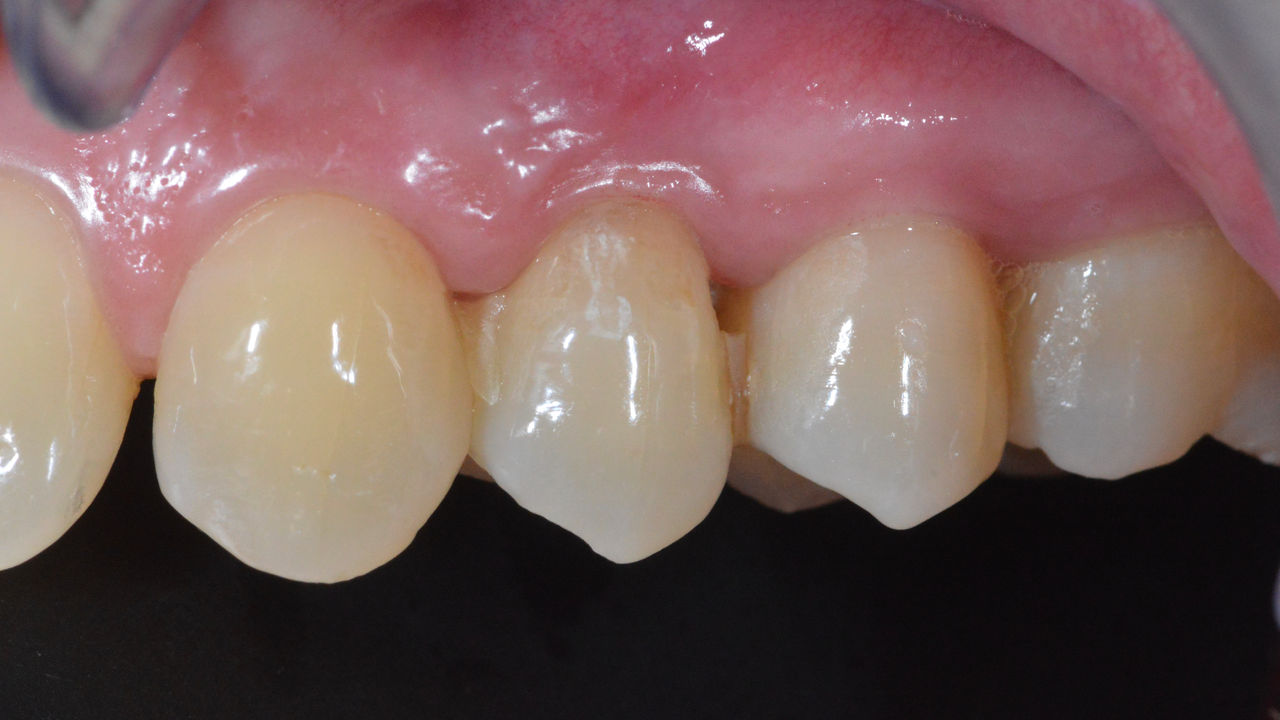

Before

Inadequate fillings on teeth 12-22, an uneven gingival line on 12 and 11 and incisal edges severely eroded.

After

Four highly esthetic and individualized lithium disilicate ceramic crowns.